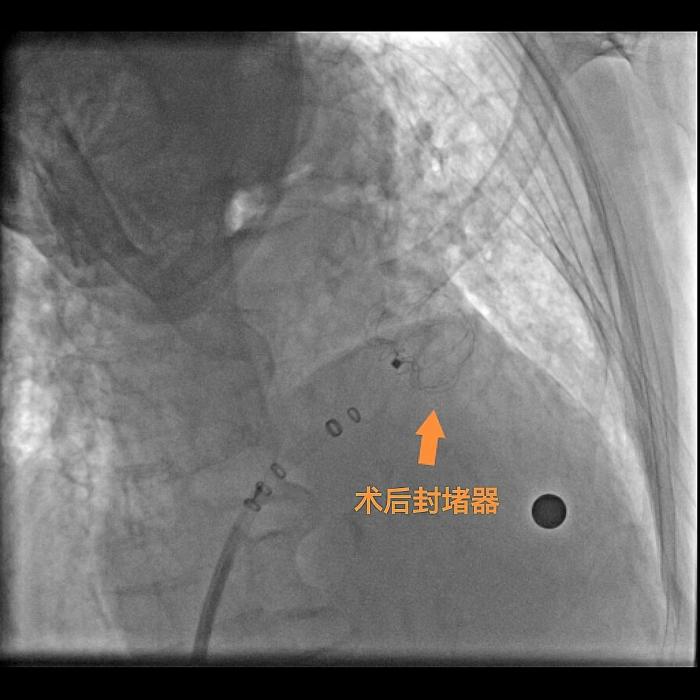

完善术前准备后,心血管内二科介入团队克服重重困难,成功为曾奶奶实施了房颤射频消融术+极简式左心耳封堵术,手术非常顺利,术后12小时患者便可下床活动。曾奶奶及家人都不由得对心血管内二科介入团队竖起来大拇指。